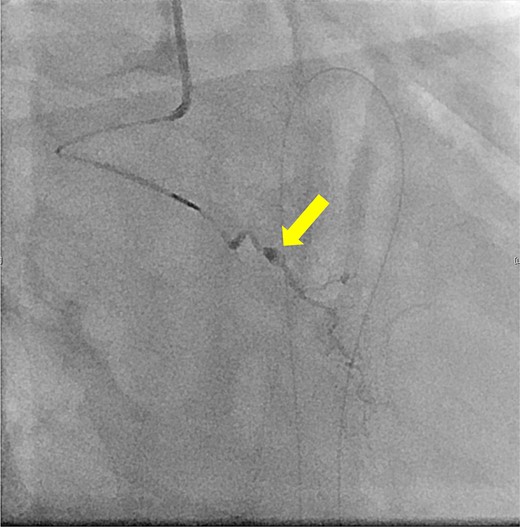

The patient underwent robotic subtotal esophagectomy, two-region lymph node dissection, narrow gastric tube was created by hand assisted laparoscopy and cervical anastomosis was performed via the retrosternal route. The operation took 613 min, with minimal blood loss. The retrosternal route under camera assist was created without bleeding, and no intraoperative hemodynamic changes or complications were observed. The pathological stage was pT1b(SM2)pN1M0 pStage II (Japanese Classification of Esophageal Cancer, 12th Edition). Esophageal fluoroscopy on postoperative day (POD) 7 showed a minor leak at the anastomotic site, which improved by POD 14 after cervical wound release and drainage. The minor leak at the anastomosis site has been the cause of prolonged hospital stay. The patient experienced sudden intermittent chest pain on POD 17, but his vital signs remained stable. Echocardiography revealed an increased amount of pericardial fluid. He was diagnosed with pericarditis and prescribed colchicine by cardiologist; however, pericardial fluid levels continued to increase. Pericardiocentesis with pericardial catheter insertion was performed on POD 34, revealing bloody pericardial fluid. Blood drainage persisted at approximately 300 ml/h. Urgent contrast-enhanced CT revealed contrast extravasation from the anterior right ventricle (Fig. 2). Coronary angiography revealed aneurysmal changes in the peripheral right ventricular branch without apparent hemorrhage (Fig. 3).

Coronary angiography reveals aneurysmal changes in the right ventricular branch without evident bleeding (arrow).